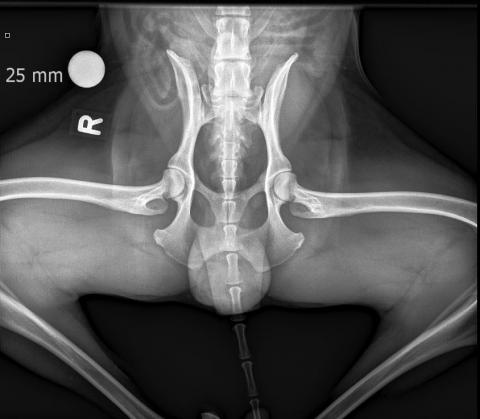

• HD Abklärungen

HD und ED Beurteilungen werden nach Wunsch des Besitzers oder nach Vorgaben der Rasseklubs jeweils von der HD-Kommission in Zürich oder Bern beurteilt. Für unsere deutschen Kunden ist auch ein Versand nach Deutschland möglich